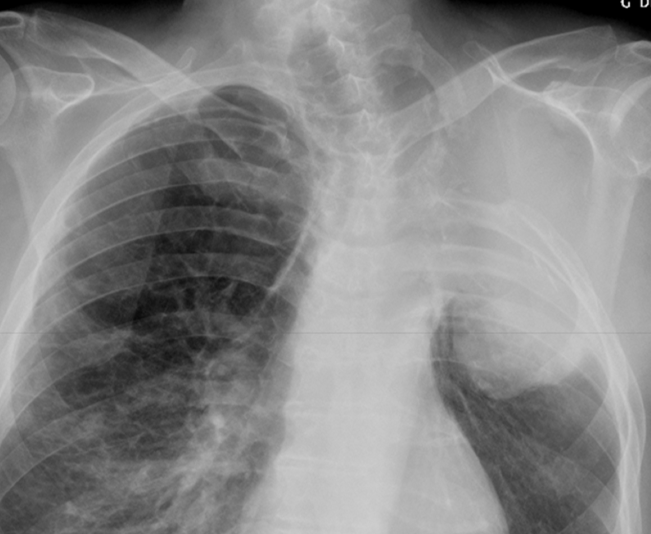

Syndrome Pleural

- Epanchement